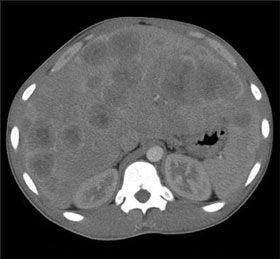

A 36-year-old woman presented to the emergency department with loss of vision in the right eye that had initially involved the peripheral field and progressed over 2 months to the central and nasal fields. During this period, she also had headaches, vomiting, and generalized weakness. She had had amenorrhea for 1 year.